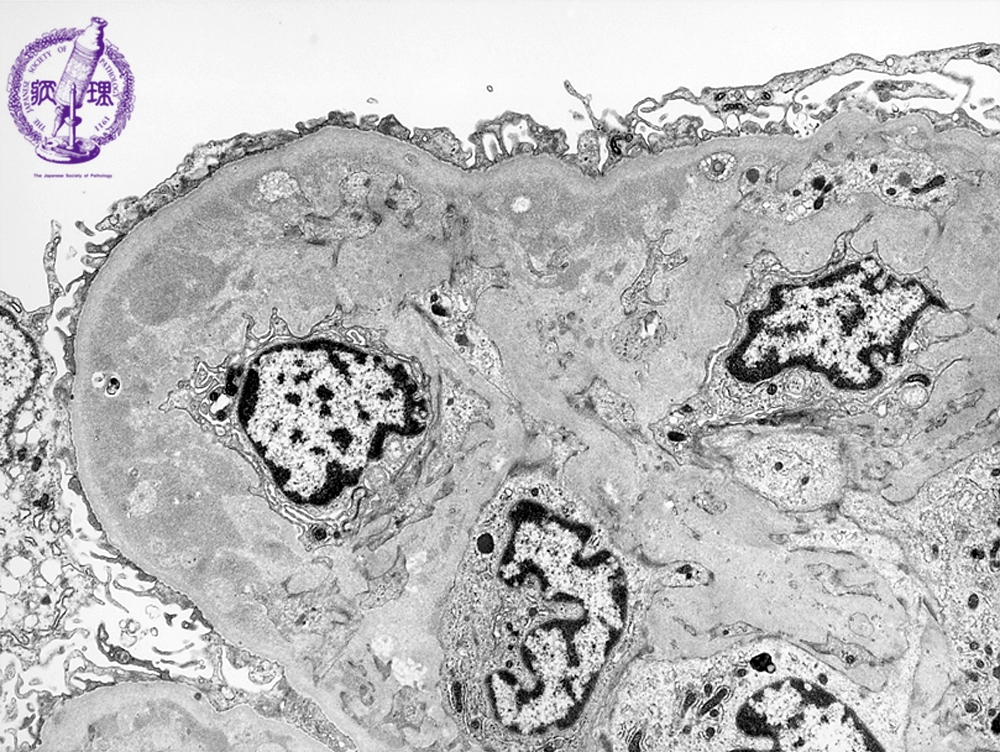

- ★(3)Membranoproliferative glomerulonephritis

Electron microscopy: Electron dense subendothelial deposits are identified (yellow dotted line).